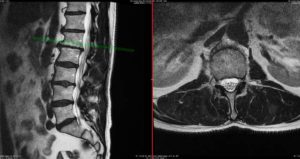

Disc displacements, often linked to back pain, can manifest as diffuse bulges or more localized herniations. Herniations are categorized into protrusions, which remain within the outer annular fibers, and extrusions, which break through the annulus fibrosus. Typically, extrusions are larger than protrusions (Fries et al., 1982).

A study by Jensen et al. (1994) involving 98 asymptomatic volunteers and 27 back pain patients found that disc bulges appeared in 52% of volunteers and 76% of patients, while disc protrusions were observed in 27% of volunteers and 54% of patients. However, these differences were not significant enough to be diagnostically useful. Notably, disc extrusions were present in only 1% of volunteers but in 26% of patients, suggesting that extrusions are a more reliable indicator of symptomatic disc lesions. Porchet et al. (2002) analyzed 394 patients with sciatica and/or back pain, finding a correlation between the severity of leg pain and disability with the severity of disc abnormalities. Conversely, studies by Karppinen et al. (2001) and Modic et al. (2005) found no clear relationship between the extent of disc abnormalities and the intensity of symptoms or disability. The conflicting findings imply that the impact of a disc herniation on symptoms depends not only on the size of the herniation but also on the spinal canal’s dimensions. For instance, at levels L4-5 and L5-S1, where most herniations occur, the spinal canal’s triangular shape offers more room centrally, making lateral recess herniations more likely to cause nerve root compression. Thelander et al. (1994) and Carlisle et al. (2005) emphasized the importance of measuring the relative size of the herniation to the spinal canal’s dimensions. Their findings indicate that larger herniations tend to necessitate surgical intervention, especially in central locations.

- Size and Location: Larger extrusions are more likely to cause symptoms, but their effect also depends on the spinal canal’s roominess.

- Nerve Root Compression: Evidence of nerve root compression is crucial and may be influenced by the patient’s posture during imaging.